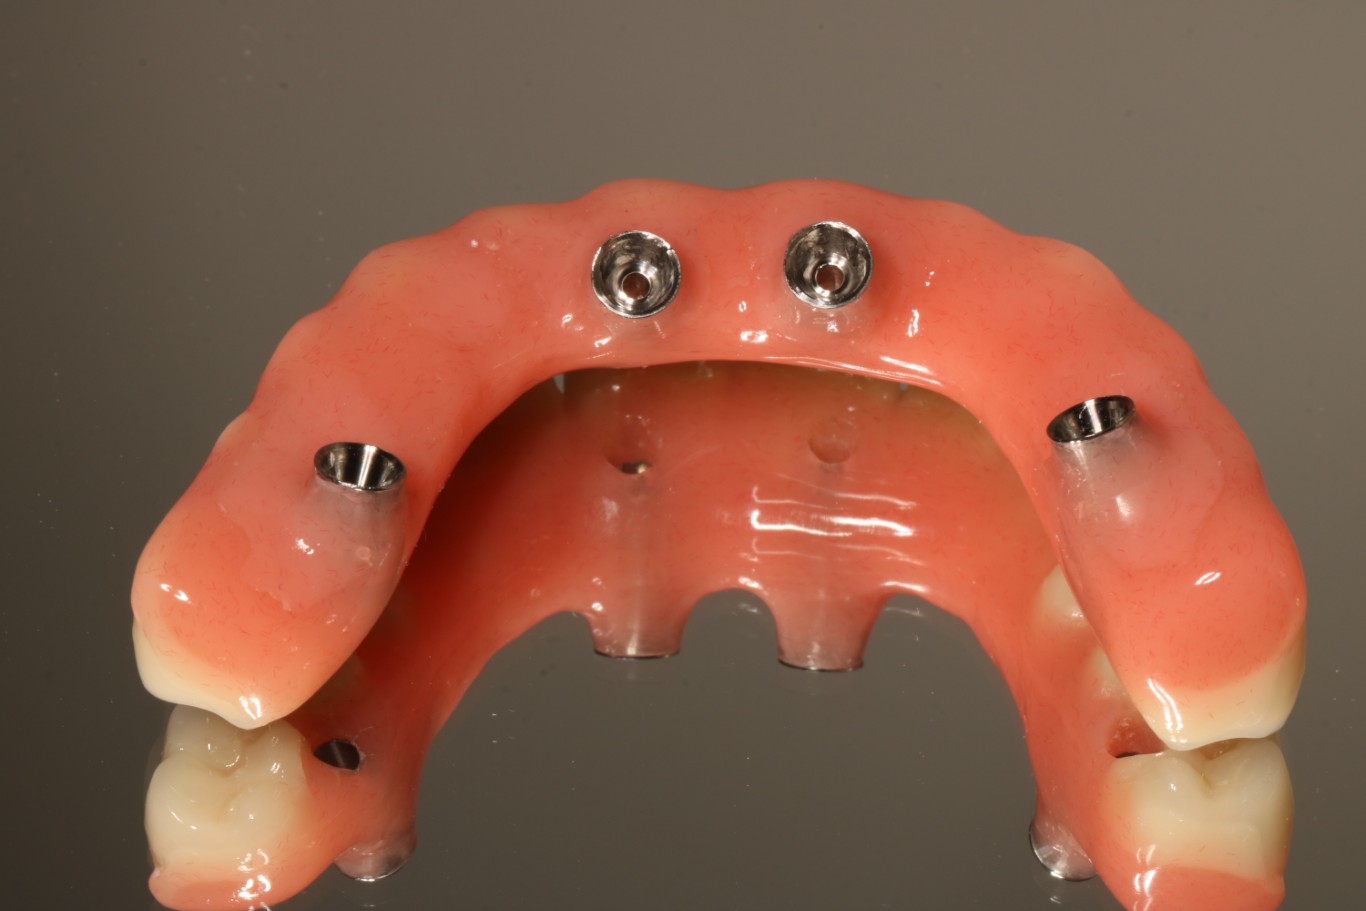

2. Protezy na belce retencyjnej – stabilność i komfort jedzenia

Protezy wsparte na belce to rozwiązanie łączące zalety implantów ze względną prostotą użytkowania. Belka retencyjna to metalowa (najczęściej tytanowa) konstrukcja przykręcona do 4-6 implantów, na której mocowana jest proteza.

Implanty zostają wszczepionych w szczękę lub żuchwę, a następnie połączone belką metalową. Proteza posiada specjalne zatrzaski lub klipsy, które mocują ją na belce – zapewniając wyjątkową stabilność, ale jednocześnie możliwość wyjęcia do higieny.

Zalety protezy na belce:

– Wyjątkowa stabilizacja – proteza nie przesuwa się podczas jedzenia, mówienia czy śmiechu. Możesz jeść twarde produkty bez obaw

– Lepsze odczuwanie smaku – duża część podniebienia pozostaje odsłonięta, język ma bezpośredni kontakt z podniebieniem, co intensyfikuje doznania smakowe

– Łatwość czyszczenia – protezy można wyjąć, dokładnie oczyścić i ponownie założyć. Implants i belka są również dostępne do szczotkowania

– Komfortowa wymowa – stabilna proteza nie zmienia położenia podczas mówienia, co eliminuje problemy z dykcją

– Stabilne utrzymanie – całkowicie eliminujemy potrzebę stosowania klejów do protez